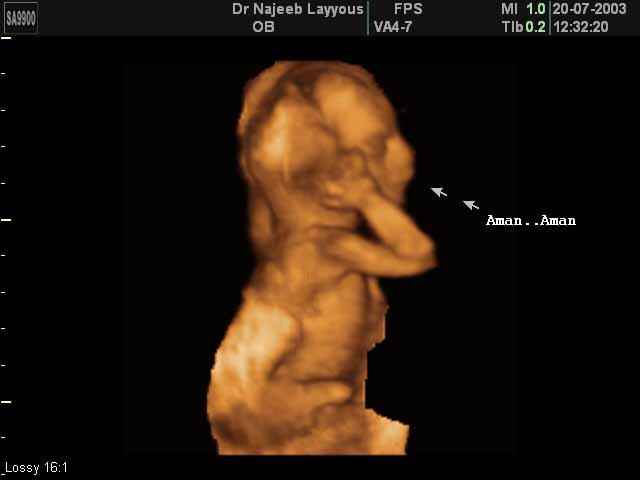

- Fetal Face Ultrasound Photos

- 3D Fetal Profile Ultrasound Scan Photos

- 3D Fetal Limbs Ultrasound Scan Photos

- Fetal Behavior Ultrasound Photos

- The Clinical Advantages of 3D and 4D Ultrasound

- Definition and Features of Four Dimensional Ultrasound

- Uses of 4D Ultrasound scan

- Fetal behavior during pregnancy

- The importance of 4D ultrasound imaging in pregnancy

3D Second Trimester Ultrasound Scan Photos-second part of pregnancy | Dr N Layyous